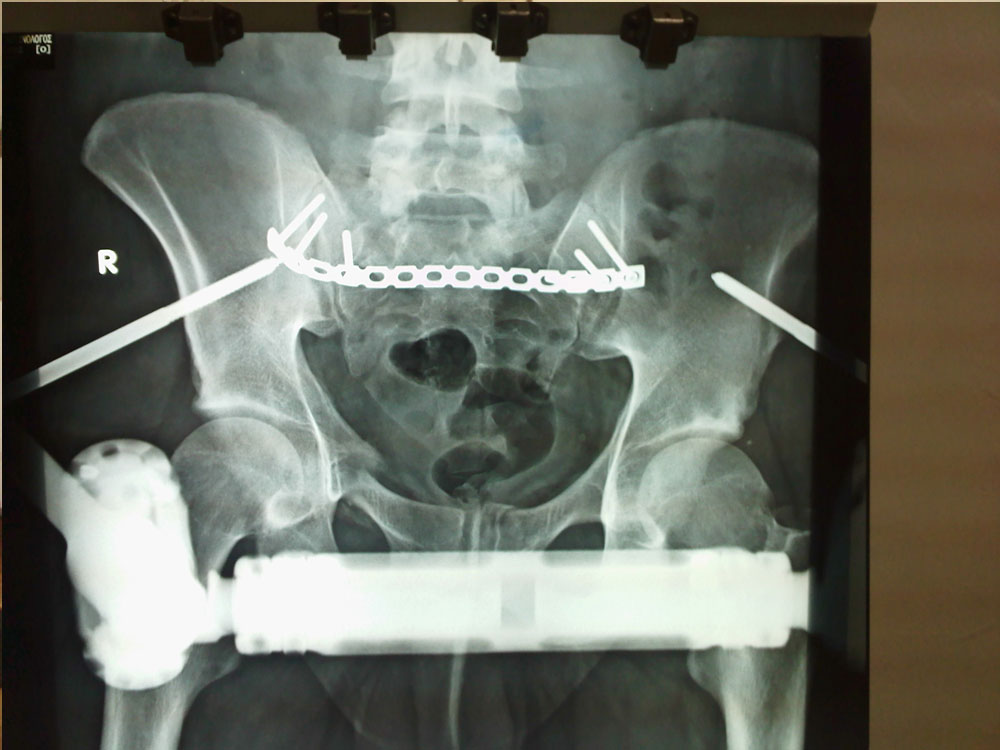

Pelvic Ring Fracture

Pelvic ring fracture (PRFs) represent 3-8% of all skeletal injuries. The annual incidence of PRFs is estimated to be 19-37 for every 100.000 inhabitants..

This type of fracture is a result of high energy injury like motor vehicle accident (MVA) or a result of low energy injury as it happens in elderly after a fall from their height.